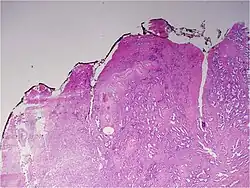

Histologic patterns

A pathologist microscopically examines the biopsy specimen for certain "Gleason" patterns. These Gleason patterns are associated with the following features:

- Pattern 1 – The cancerous prostate closely resembles normal prostate tissue. The glands are small, well-formed, and closely packed. This corresponds to a well differentiated carcinoma.

- Pattern 2 – The tissue still has well-formed glands, but they are larger and have more tissue between them, implying that the stroma has increased. This also corresponds to a moderately differentiated carcinoma.

- Pattern 3 – The tissue still has recognizable glands, but the cells are darker. At high magnification, some of these cells have left the glands and are beginning to invade the surrounding tissue or having an infiltrative pattern. This corresponds to a moderately differentiated carcinoma.

- Pattern 4 – The tissue has few recognizable glands. Many cells are invading the surrounding tissue in neoplastic clumps. This corresponds to a poorly differentiated carcinoma.

- Pattern 5 – The tissue does not have any or only a few recognizable glands. There are often just sheets of cells throughout the surrounding tissue. This corresponds to an anaplastic carcinoma.

In the present form of the Gleason system, prostate cancer of Gleason patterns 1 and 2 are rarely seen. Gleason pattern 3 is by far the most common.